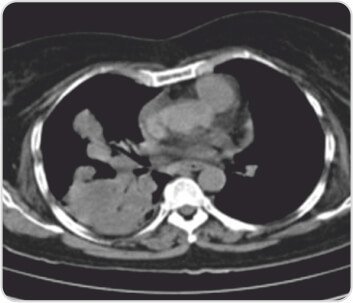

CT scan of chest showingRight lower and middle lobe consolidation